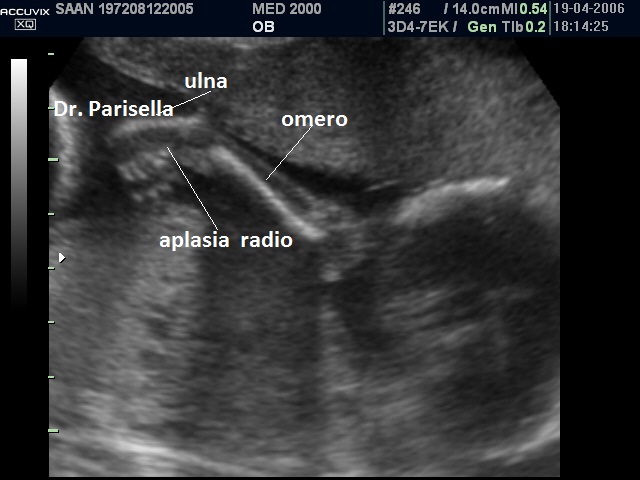

aplasia radio

La displasia boomerang รจ una sindrome estremamente rara caratterizzata da nanismo micromelico con arti ricurvi e rigidi, difetti di ossificazione, aplasia della fibula, aplasia del radio, facies caratteristica con radice del naso ampia ed ipoplasia delle narici e del setto nasale.